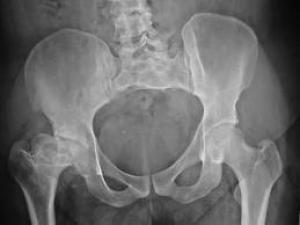

Dutch researchers recently revealed that patients with metal-on-metal total hip replacement systems may be at a 10 percent greater risk for developing pseudotumors.

First, you may wonder, what is a pseudotumor? According to online sources, inflammation or fluid accumulation may cause a tumorlike mass. The study – published in Britain’s Journal of Bone & Joint Surgery – said metal-on-metal hip replacement patients may experience pseudotumors that produce pain, swelling, clicking.

Out of 119 patients who underwent the surgery between January 2005 and November 2007, a total of 108 were eligible for a CT scan. Of those, 42 patients were diagnosed with a pseudotumor.

Thirteen patients underwent hip revision surgeries with a polyethylene acetabular component after it was revealed that these patients suffered from metal poisoning, swelling, necrosis, or a large semi-tumor from their metal-on-metal replacement. Those with high serum metal ion levels were four times more likely to develop a pseudotumor than those with lower levels.

Metal-on-metal hip replacements have been under close scrutiny by both researchers and the FDA since these devices have been linked to a number of serious complications. Companies like Johnson & Johnson were forced to issue recalls due to metal poisoning and high failure rates.